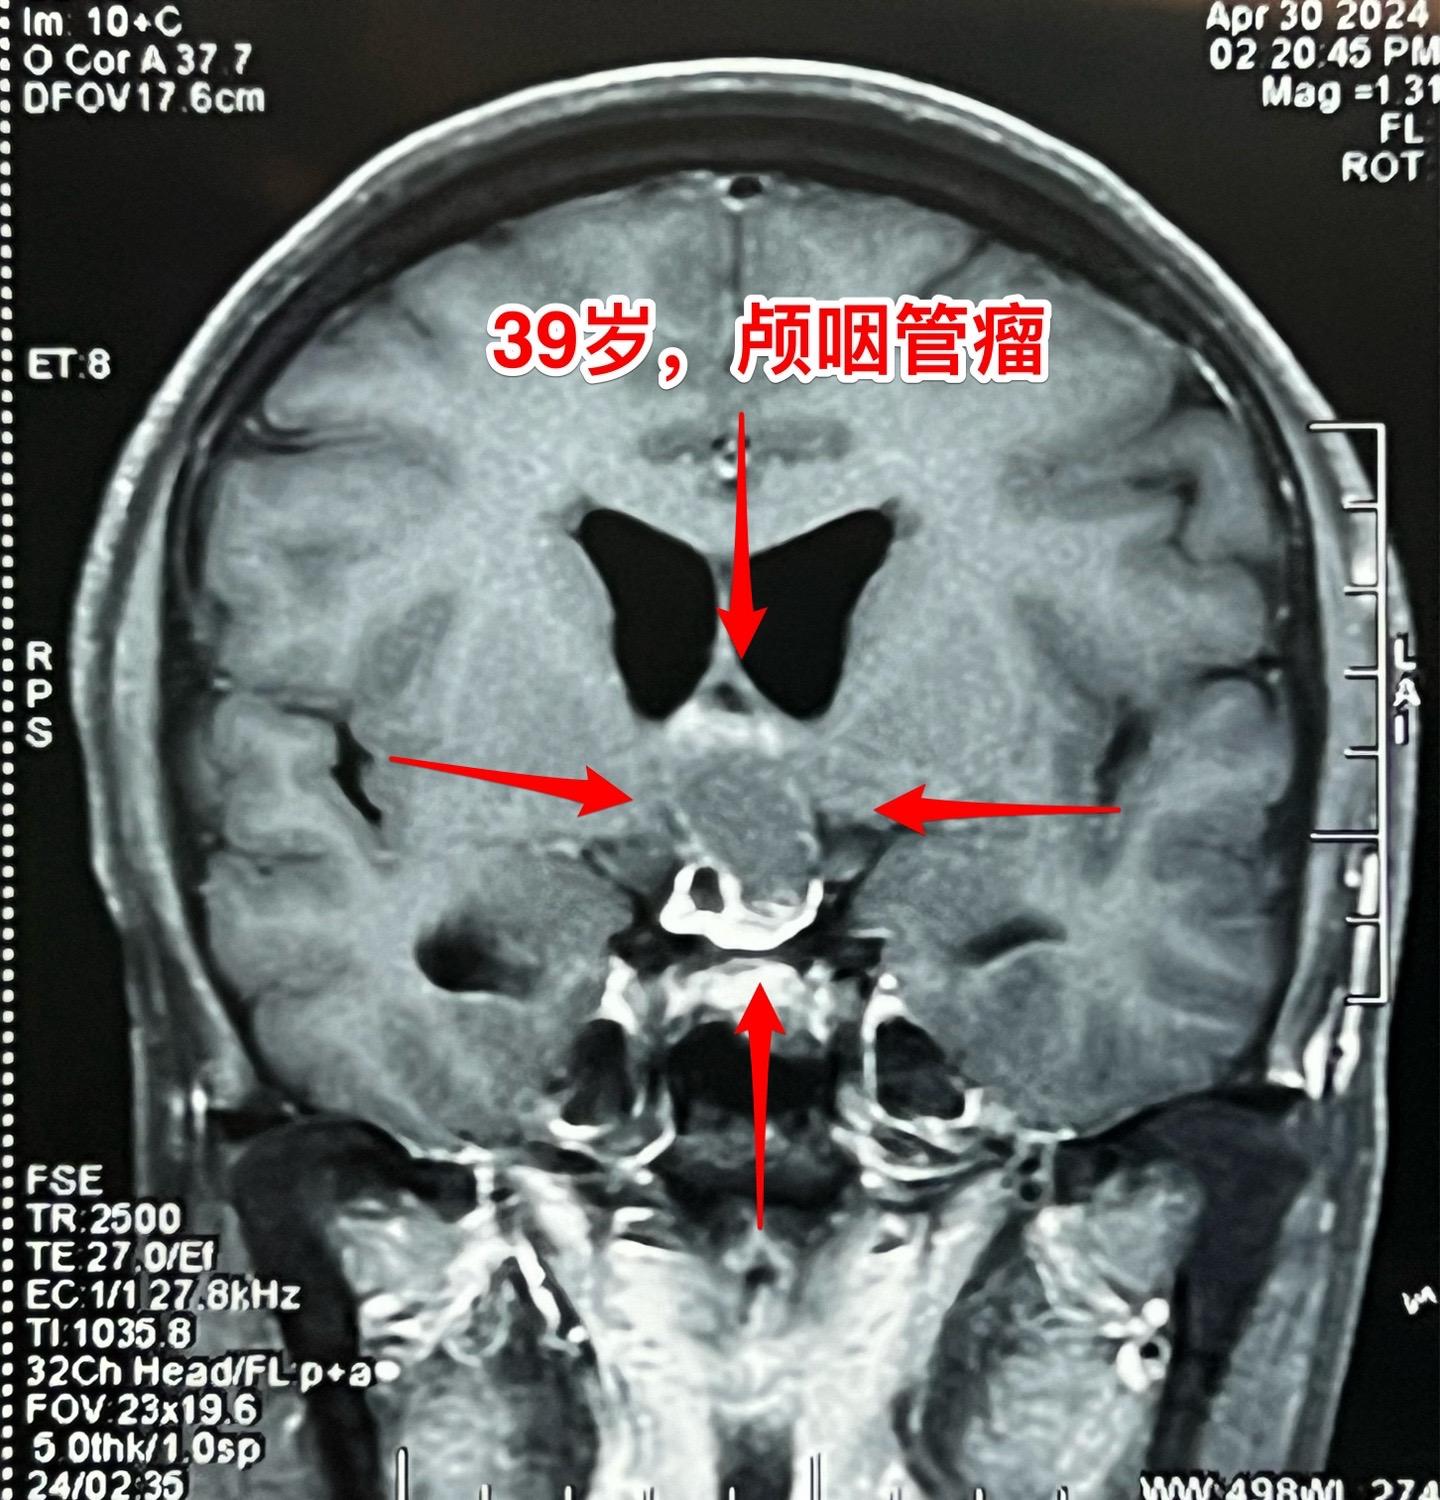

五月六日的颅咽管瘤手术。山西省男性,39岁,因为头痛、呕吐在4月29日就急匆匆的赶到三博脑科医院来住院。病因是颅咽管瘤造成颅压高,不能正常吃东西了。住院后用药物治疗,头痛症状减轻,也不呕吐,能正常进食。从图片可以看出这个颅咽管瘤属于细长型,从垂体窝延伸到第三脑室内,垂体窝里有大块钙化,手术是有难度的。 五一假期一过就排上手术,顺利切除肿瘤,手术后CT结果很让人满意,希望肿瘤不复发。